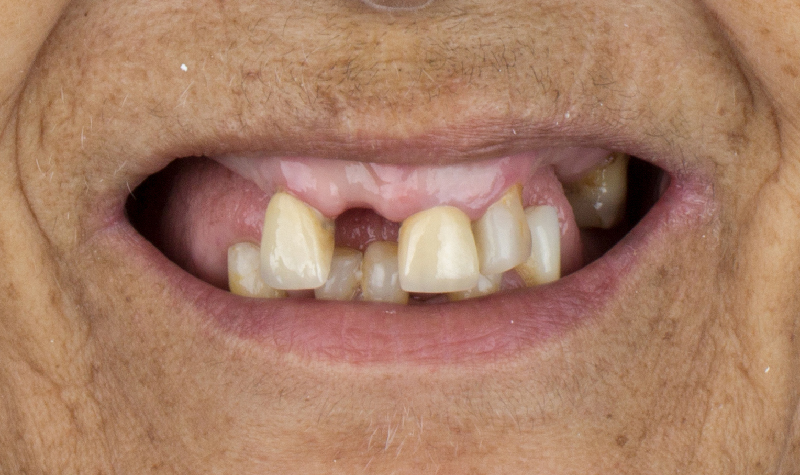

Rehabilitación oral total de alta complejidad con cerámicas sobre dientes e implantes.